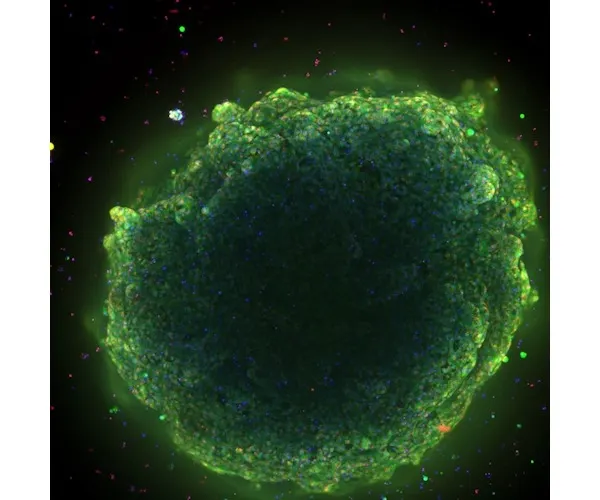

肝臓オルガノイドは、前臨床段階で薬剤性肝障害をおよそ80%の精度で予測します。オルガノイドを用いた薬剤性肝障害の予測は、薬剤の安全性を向上させ、新しい治療法の発見を加速し、薬剤障害の主な原因をより迅速に特定することができます。ダナハー、モレキュラーデバイス、シンシナティ小児科の幹細胞・オルガノイド医学センター(CuSTOM)の協力により、肝臓オルガノイドのスケールアップ生産を可能にするハイスループット技術が実現します。これには、細胞バンクを構築し、ヒトの遺伝子をよりよく反映させ、臨床試験における多様性を向上させる構想も含まれています。

オルガノイド科学を発展させるために私たちが抱いている中核的な信念は、オルガノイドの生成から当て推量を取り除くことです。CellXpress.aiプラットフォームのような自動化技術の設計は、その信念を支えるものです。例えるなら、このテクノロジーは、細胞を入れるとオルガノイドが出てくるオーブンのようなものです。オーブンに例えるなら、すぐに使えるケーキミックスが理想的なアプローチです。このエンドツーエンドを達成するために、私たちは、スクリーニング・ツールとして使用するためにスケールアップする際に再現性と一貫性を確保できるよう、標準的な方法と品質管理を浸透させることによって、次のレベルに引き上げることに注力してきました。

方法、培地、プロトコルを微調整するために、かなりの量の作業を前もって行う必要があります。これは、何かが革新的なモデルから主力技術へと進歩するための基本的な側面です。例えば、ある患者のセルに特異性レベルで作用するように最適化された方法が、別の患者に合うように条件を調整する必要がないとは限りません。スケーラビリティの問題に対処するために必要なのは、大規模な患者サンプル集団で機能する適切な方法と条件を見つけることです。これがCuSTOMが完成させる作業です。完成後は、細胞が穏やかに扱われ、ストレスを受けず、自発的に分化していることなどを確認するために、結果を検証する必要があります。モレキュラーデバイスは、当社のCellXpress.aiプラットフォームと専門知識を活用して支援します。

特異的な薬剤性肝障害など、ある種の肝臓の感受性は、遺伝的要素が大きいのです。セルが行っているのは、例えば、さまざまな民族の患者を集めた細胞バンクの設立です。これは、低リスク、中リスク、高リスクの患者からオルガノイドを作製し、試験管内で薬物治療後のシグナルが見られるかどうかをテストする対物レンズによるスクリーニング・プラットフォームの基礎となります。このアプローチを用いれば、科学者は臨床試験に入る前に、何を調べるべきか、どのように投与量を設定すべきか、どのようにスクリーニングすべきか、基本的にはどのようにリスクをより効果的に軽減すべきか、がわかるようになります。これは非常に重要なことです。皿の中の患者という概念。生体内に入る前に、実際に何が起こるかを知ることができますか?複雑なモデルやオルガノイドのような概念が真に輝くのはこの点です。